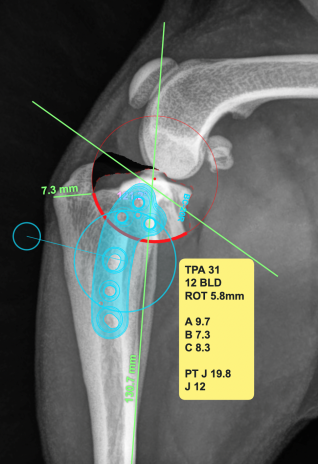

Abmessungen und genaue virtuelle Planung der OP anhand der Röntgenbilder

Die Therapie erfordert in der Regel eine operative Versorgung des Gelenkes. Die bevorzugte Methode ist die Tibial Plateau Leveling Osteotomy (TPLO). Bei dieser chirurgischen Methode wird der Tibia-Plateau Winkel verändert, um die Neigung zu neutralisieren. Das Gelenk wird dadurch langfristig stabilisiert, was die Schmerzen eliminiert und das Fortschreiten der Arthrose minimiert.